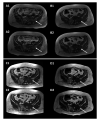

Results: 29 patients with locally advanced and/or metastatic GCTB treated with denosumab were identified. At a median follow-up of 70 months (range 1-125), 4 (13.8%) patients experienced MR-ONJ while on treatment, after 125, 119, 85 and 41 months of denosumab, respectively. All patients showed an ongoing tumour stabilisation with denosumab at the MR-ONJ onset and in all cases denosumab was stopped. All four patients were treated with ozone therapy. Two are waiting for surgery, two were already operated on. Both of them experienced disease progression and were thus rechallenged with denosumab. One is still on therapy after 25 months. The other had an MR-ONJ relapse after 39 months and was treated again with ozone therapy and surgery. She is under surveillance, GCTB being currently stable.